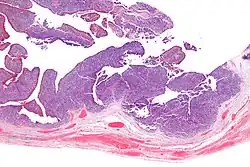

Micrograph of transitional cell carcinoma of the ovary. H&E stain.

TCC of the ovary is diagnosed by examination of the tissue by a pathologist. It has a characteristic appearance under the microscope and distinctive pattern of immunostaining.[2]